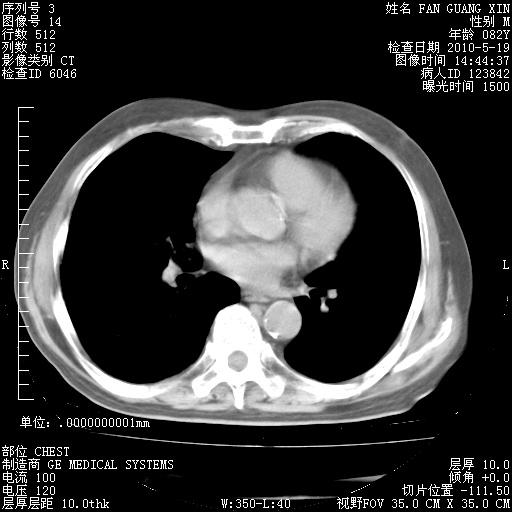

治疗3周后的肺部CT纵隔窗